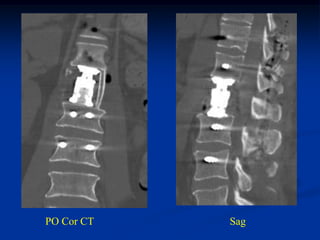

PO Cor CT   Sag